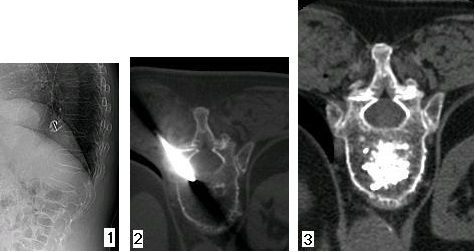

Figura 1 - Paziente di 73 anni, affetta da dorsalgia da oltre 2 mesi, non controllabile con la terapia medica e con il busto. L'esame radiografico fa apprezzare sul piano sagittale l'avvallamento della limitante somatica superiore della XII vertebra toracica. In corrispondenza della stessa si evocava una spiccata dolorabilità alla digitopressione e all'esame di risonanza magnetica si apprezzava la presenza di edema intraspongioso nella sequenza STIR.

Figura 2 - Le piccole dimensioni e l'orientamento pressoché sagittale dei peduncoli hanno fatto preferire l'accesso trans-costovertebrale che è possibile eseguire e monitorare sotto guida TC con estrema efficacia e sicurezza (come dimostra l'immagine).

Figura 3 - L'esame TC, assunto dopo l'iniezione del cemento eseguita sotto guida scopica, fa apprezzare la corretta diffusione del cemento all'interno del corpo vertebrale e l'assenza di fuga dello stesso nei tessuti contigui.